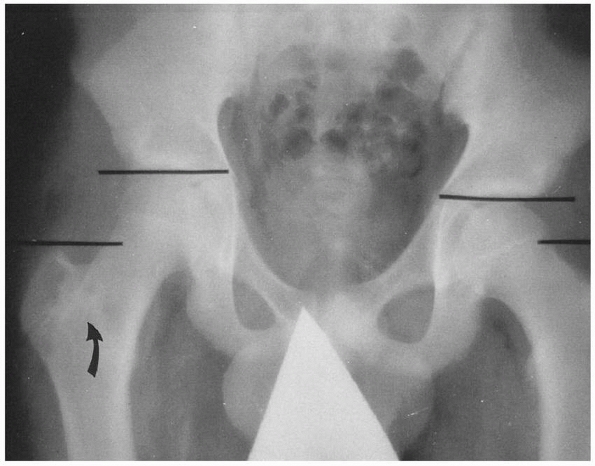

including the hip and knee, because injury of the adjacent joints is

common. An anteroposterior (AP) pelvic x-ray is a valuable supplement

to standard femoral shaft views, because there may be an associated

intertrochanteric fracture of the hip, fracture of the femoral neck, or

physeal injuries of the proximal femur.13,31 Distal femoral fractures may be associated with physeal injury about the knee, knee ligament injury, meniscal tears,202 and tibial fractures.121